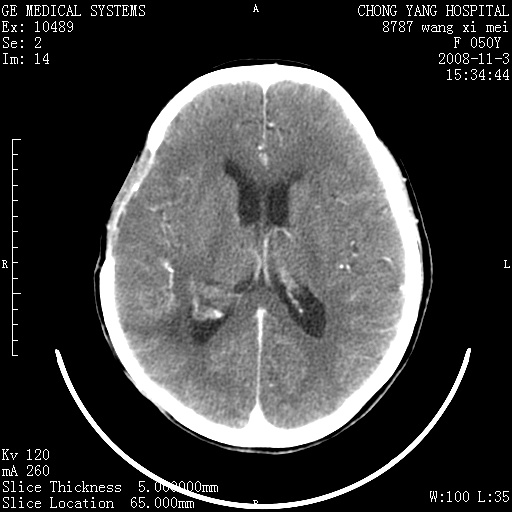

标题: CT16469:女,50岁,胶质瘤术后6年,今平扫加增强,请大家帮 [打印本页]

标题: CT16469:女,50岁,胶质瘤术后6年,今平扫加增强,请大家帮

右颞骨局限性缺如,局部脑组织无外隆。右颞叶可见片状脑脊液样低密度影,边缘较清,右侧侧脑室三角区可见一块状等密度影,且伴有强化,余未见明显异常改变。

考虑:右大脑术后改变伴肿瘤复发。

手术后局部片状低密度改变(软化灶),其后方颞叶似等密度病灶,界限不清,内见钙化,有轻度占位效应,但增强后强化之血管走行如常。应不考虑:复发!

应考虑肿瘤复发,右颞顶叶已出现轻度强化肿块.必要时可与原片比较以下.

局部软化灶并钙化;无花边样强化,不象复发